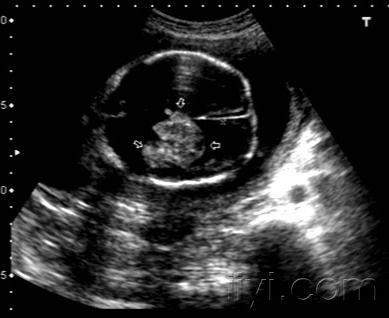

【图示 手绘】读懂正常胎儿颅脑超声

正常胎儿颅内结构图

胎儿脑部超声切面图解

胎儿第三脑室超声图片